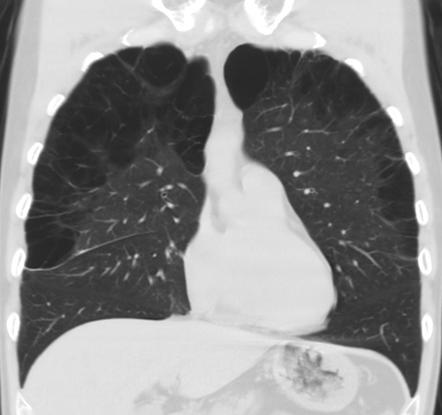

Рентгеновские снимки при врожденной эмфиземе легкого

Раздел: Визуальные уроки